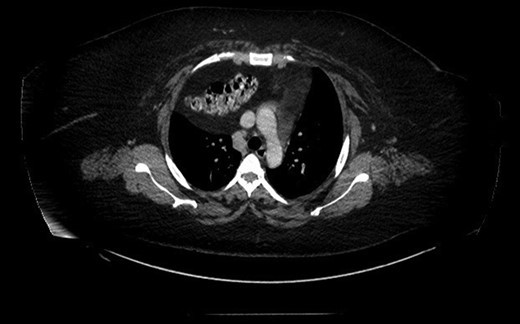

Prior to the surgery patient had symptoms of mild dyspnea, vague abdominal discomfort and an initial evaluation with Chest X Ray revealed bowel gas pattern in the right hemithorax (Fig. 1). A subsequent CAT scan thorax and abdomen revealed a right-sided large morgagni diaphragmatic hernia containing omentum and portion of the transverse colon (Fig. 2). Patient elected to undergo Laparoscopic sleeve gastrectomy and concomitant morgagni diaphragmatic hernia repair. Abdomen was explored laparoscopically which revealed a right sided morgagni diaphragmatic hernia with defect size about 8 × 4 cm, containing omentum, transverse colon and part of the falciform ligament. Contents were reduced successfully taking care not to injure the bowel, falciform ligament partially dissected. A sleeve gastrectomy done. Then the hernial defect was closed primarily by interrupted non absorbable sutures. The closure was then reinforced with a sublay ventralight mesh which was secured using transfascial fixation sutures and with tackers (Fig. 3). The post operative course was unremarkable and the patient was discharged on post operative Day 2 with normal chest X-ray (Fig. 4). At 2 months after surgery the patient was doing well and tolerating solid and liquid diet and no more dyspnea nor GI symptoms.